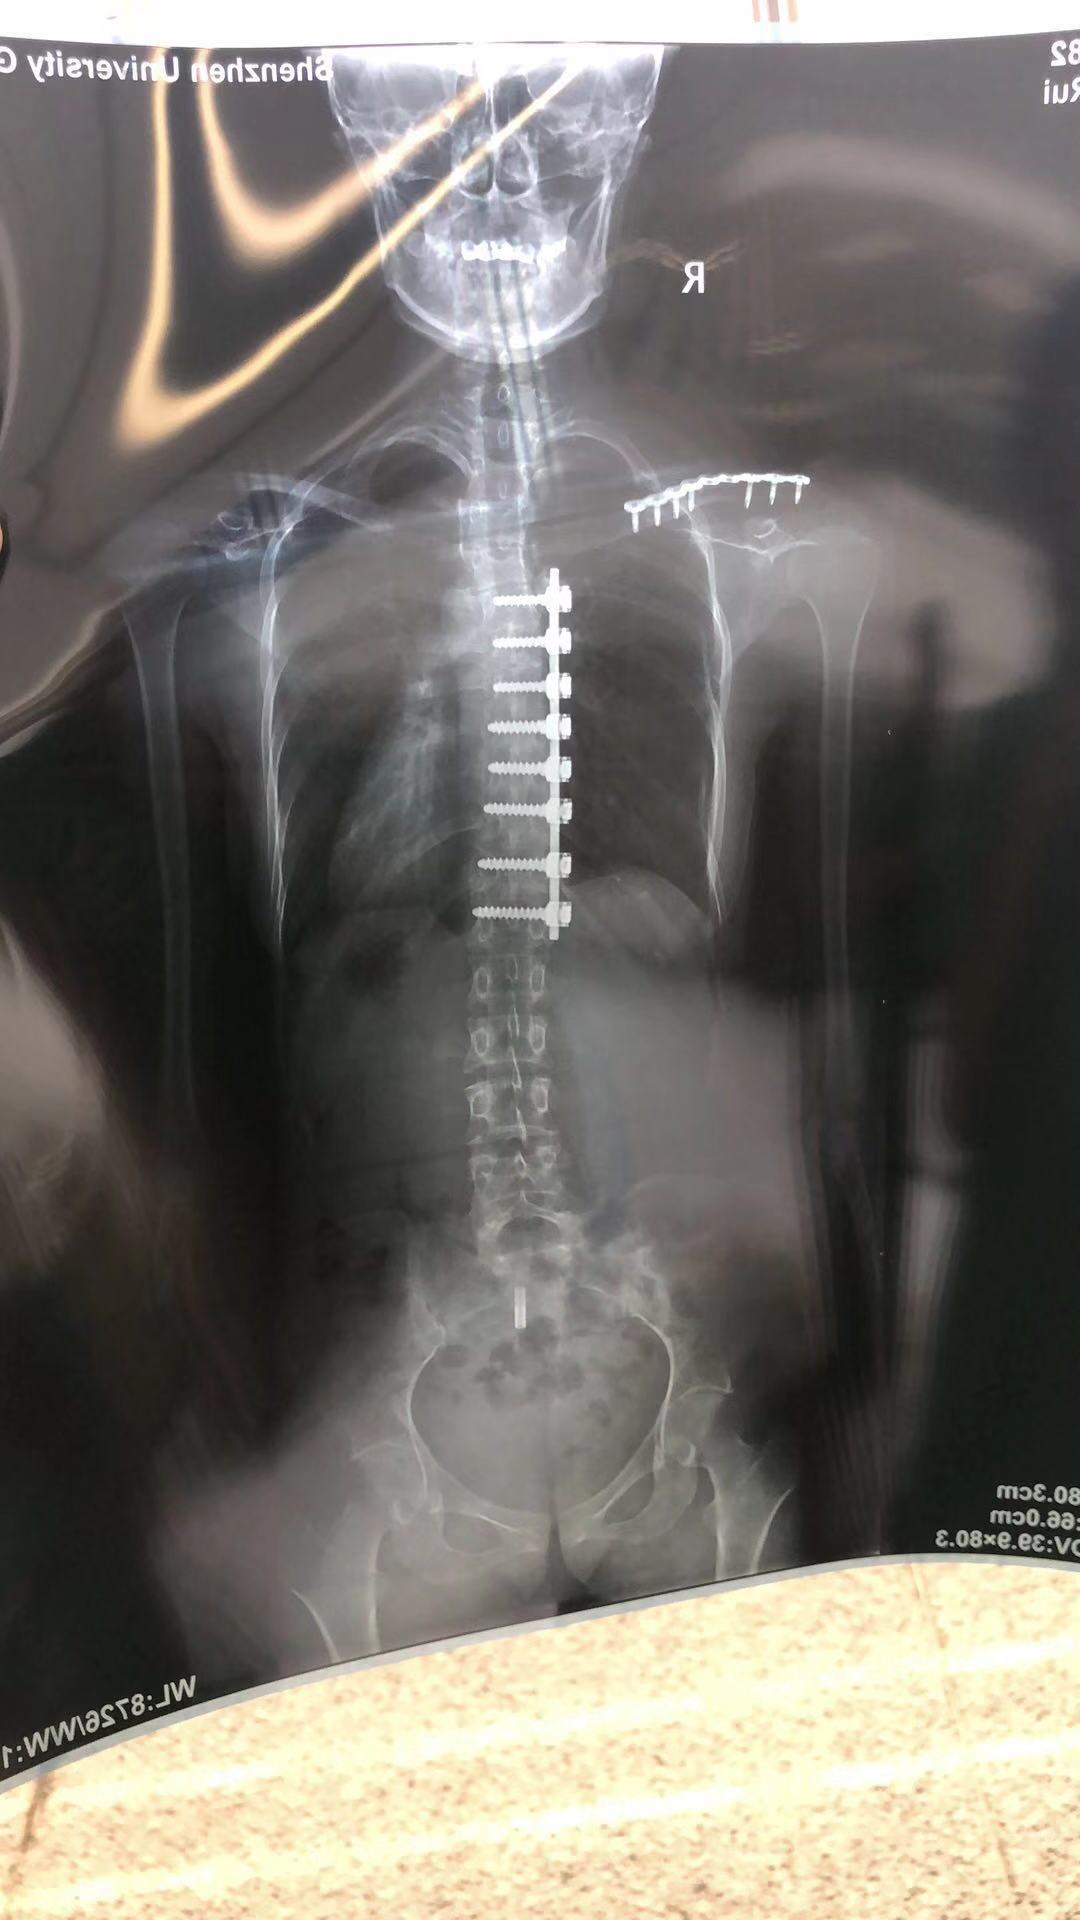

真的非常非常感激教授!他为了让我的刀口小一点,为我做了“胸腔镜下矫正手术”。而这个手术方案是在侧面开刀,只切开几厘米的口子,然后用他那双巧手去完成了如此高风险的大手术。

如今我已经术后9年多了,可以穿任何我想穿的衣服,后背没有疤痕,比基尼都没有问题。